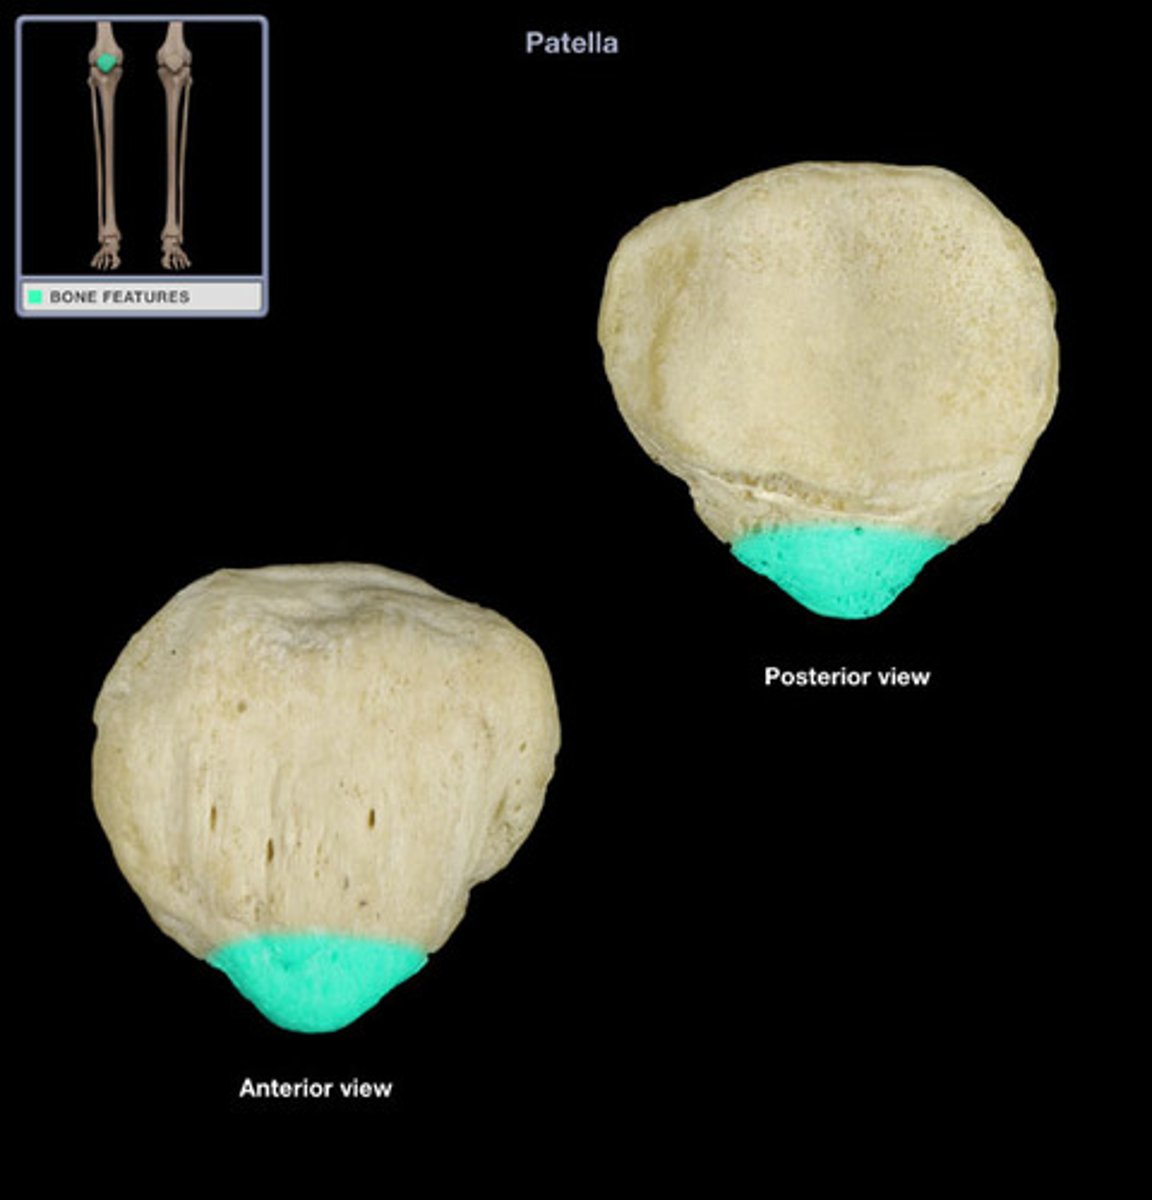

Patella

Apex

inferior surface for patellar ligament

Base

superior surface for quadriceps tendon